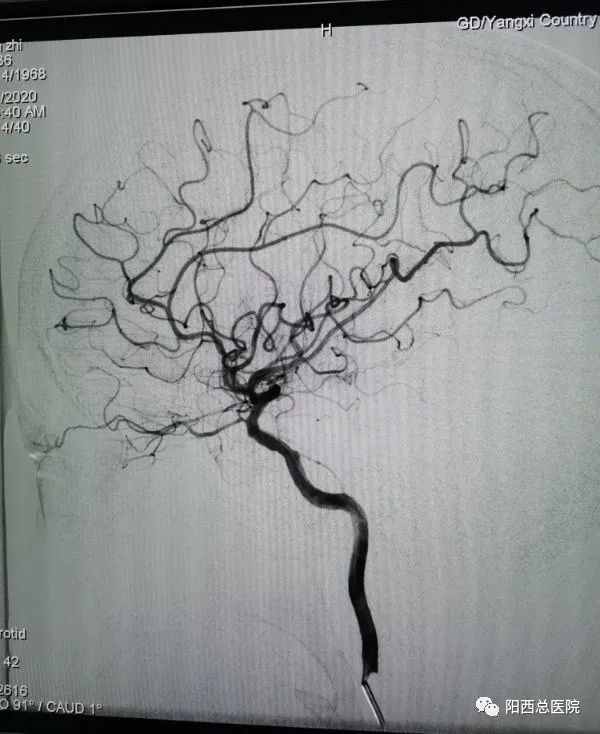

阳西沙扒的陈叔今年52岁,用老伴的话说除了长期吸烟外没什么毛病,下地干活、外出做工样样出色。可就在这几天,陈叔突然出现右侧肢体无力,右手持物不稳,不能走路,伴言语欠清。家人立即将陈叔送到阳西总医院县人民医院。脑科中心莫锡尚医生迅速为患者完善头颅CT检查,明确诊断陈叔为“急性缺血性脑卒中”,NIHSS评分7分。由于陈叔送医比较及时,在急性缺血性脑卒中静脉溶栓的时间窗内,阳西总医院脑科中心卒中团队在由中山大学孙逸仙纪念医院神经内科雷鸣博士、神经外科外科王圣文博士组成的帮扶团队带领下,第一时间查看病人后,排除了禁忌症,快速制定治疗方案:马上进行“阿替普酶”静脉溶栓。在患者溶栓治疗的同时,结合患者的病史、临床表现,考虑大血管病变可能性大,可进行桥接治疗。征得家属同意后,脑科中心立即将患者送至介入中心行全脑血管造影术。术中颅内未见大血管闭塞,术后NIHSS评分3分,说明静脉溶栓取得显著效果。